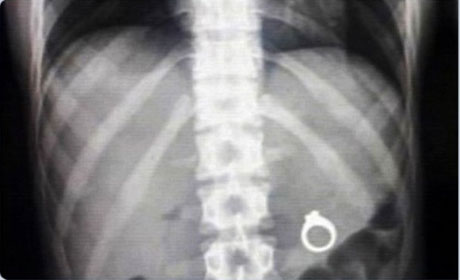

Mədəsindən əl bombası çıxdı - ŞOK FOTOLAR

İnsan nələri udmağa qadir deyil? Yaxud mədədən nələr gəlib-keçmir? ANN.Az-in oxuculara təqdim etdiyi fotolar bir daha insanın nələrə qadir olduğunu göstərir. 1. İlan balığı2. Qaşıq3. Batareyalar4. Canlı qurbağa5. Mismar6. Dərmanlar 7. Nişan üzüyü8. Qayçı9. Tük yumağı10. Mobil telefom11. Qələm12. Yay13. Əl bombası14. Açar15. Lampa